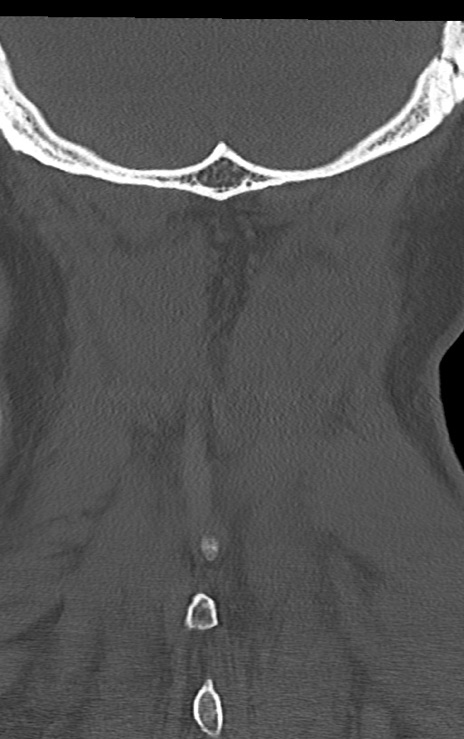

頚椎CT

矢状断像